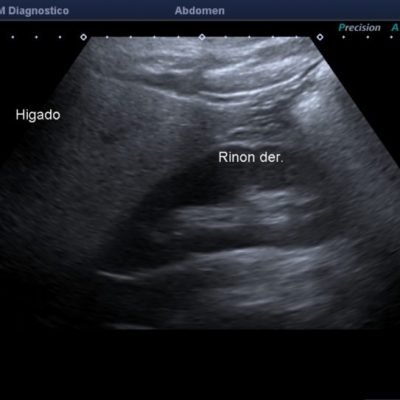

El médico de referencia le indica nueva ecografía de control, donde se observan múltiples y extensas lesiones focales hepáticas hiperecogénicas, redondeadas y confluentes, las cuales predominan en adyacencia a venas supra hepáticas, sin condicionar efecto de masa y sin alteración de la superficie hepática(fig. 1 y 2). Ante la valoración con Doppler color no presenta patrón de flujo peri ni intralesional y respeta el calibre de las venas supra hepáticas(fig. 3 y 4). Dada las características ecográficas se sospecha esteatosis focal multinodular confluente como principal diagnóstico presuntivo, siendo los diagnósticos diferenciales patologías de naturaleza infecciosa, tumoral o metastásica.